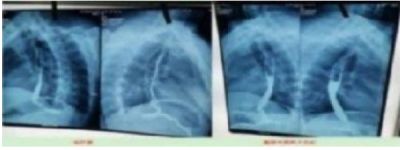

案例4、右肺上叶癌(左侧颈部淋巴结转移、鳞状细胞癌)

患者岂六荣,53岁,系山西省晋中市左权县石匣乡管头村,于2013年1月9日前来就诊。因左胸憋闷,右肺呼吸困难,后背呈放射性疼痛近日加重。于2012年8月7日就诊于山西医科大学第一附属医院,行胸部CT示:右肺上叶癌,行气管镜示;右上叶后段支气管肺癌,右上叶支气管与右中间支气管分膌,右中间支气管开嗳累,病理回报:鳞状细胞癌(病理号12-12929)。于8月30日就诊于山西省肿瘤医院接受治疗。经该院各项检查最后诊断:右上叶癌: 左侧颈部淋巴结转移,鳞状细胞癌,化疗后出院于2012年9月19日转山西武警总医院(第一次入院),2012年9月19日。住院期间经过完善的相关检查,期间出现血小板低下,给予升血小板治疗后,血小板恢复正常,后行伽玛刀治疗后,同时给予中药抗肿瘤药今患者及家属要求出院,于2012年10月10日家属要求出院,住院21天。出院诊断;1、右肺上叶癌2、左侧颈部淋巴结转移3、血小板低下,白细胞低下4、乙型肝类(恢复期)。第二次住院(2012年11月9日)出院(2012年11月21日)共住院12天。今患者及家属要求出院,于今日自动出院。

于2o13年1月8日一2o13年5月28日纯中药临床治愈,14o天清零。停药一年半后做医学鉴定:未见肿瘤细胞。至今11年未見复发,未見转移,不服药。一直从事农业劳动。于2024年2月10日(春节)上午10点接通岂六荣电话时,他正赶着羊群往后山上的路上,当我问到中午吃饭怎样解决时:因后山上离村有六七里山路,只有随干粮充饥,并告诉我每天上午10点准时出犮,下午4点半就回到家了。当我问到他身体时:"自从在您那里治好后十一年至今天,不复发,不服药。我很好,很健康,请陈大夫放心”。今天是过大年,你们早点回去,给您拜年,祝您全家新年快乐,平安,幸福!